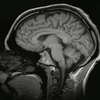

بوابة العقل و الدماغ تتناول موضوعا متشعبا يدرس في عدة حقول : العلوم العصبية و فلسفة العقل و اللسانيات و علم النفس .

العلوم العصبية هي الحقل الذي يدرس و يتعامل مع البنى العصبية , الوظائف العصبية , التطور العصبي , علم الجينات , الكيمياء الحيوية , الفيزيولوجيا , علم الأدوية , إضافة إلى علم الأمراض العصبي .

يطلق عليه أيضا اسم البيولوجيا العصبية حيث يندرج ضمن الطب و يدرس الظواهر المخية. فقد أكتشف مثلا أن عدد الخلايا المخية لا يتغير تقريبا مع الزمن ولكن الذي يتغيير هو كيفية تواصل و تلاحم هذه الخلايا. فكلما درب المرء نفسه و أجهد دماغه بالتفكير كلما زاد عدد الوصلات و إلتحامها و هو ما يؤدي إلى مقدرة أكبر على الإستيعاب و الذكاء و العكس بالعكس.

الدراسة البيولوجية للدماغ البشري يشكل أساس هذا الحقل المتداخل الذي يتضمن العديد من مستويات الدراسة , من المستوى الجزيئي إلى المستوى الخلوي (العصبونات المفردة) , إلى مستوى التجمعات الصغيرة نسبيا من العصبونات مثل cortical columns , و الجمل الفرعية الأكثر تعقيدا مثل ساحات الإدراك البصري visual perception , و حتى الجمل العصبية الضخمة مثل القشرة المخية cerebral cortex و المخيخ cerebral cortex كأعلى مستويات التعقيد ضمن الجهاز العصبي .